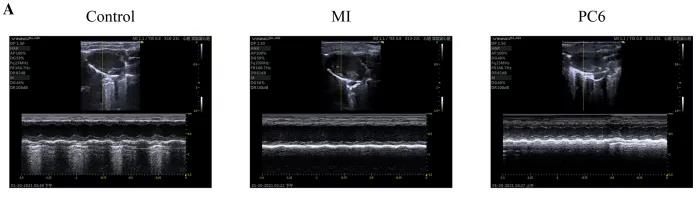

為了探討針刺PC6穴對(duì)心肌損傷的影響,作者首先評(píng)估了心功能和梗死面積。超聲心動(dòng)圖結(jié)果顯示MI組的EF(ejection fraction)和FS(fractional shortening)均較對(duì)照組明顯降低。PC6穴位治療后,EF和FS均增加。針刺治療5天后, 采用TTC染色檢測(cè)梗死面積。結(jié)果顯示,針刺治療顯著減小心肌損傷的大小。采用ELISA法測(cè)定反映急性心肌損傷的心肌特異性血清酶,包括心肌肌鈣蛋白T (cTnT)和心肌肌鈣蛋白I (cTnI)的水平。結(jié)果表明,心肌梗死術(shù)后cTnT和cTnI水平升高,針刺可顯著降低血清酶水平。